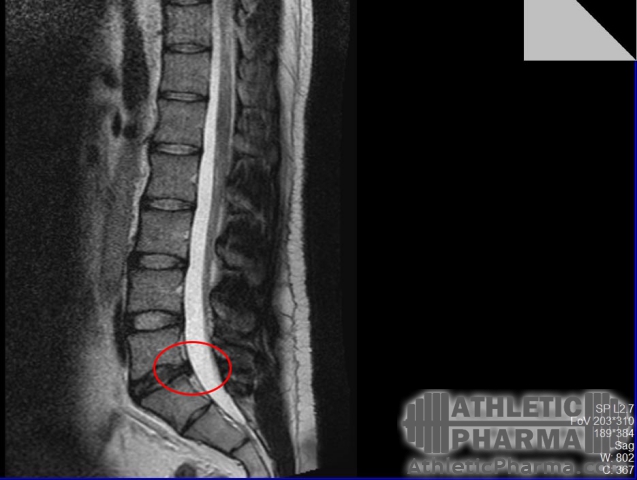

Сделал МРТ(был 80кг), межпозвоночная грыжа 5мм в сегменте L5-S1, признаки остеохондроза

med_gallery_26_2_34094.jpg

Сделал МРТ(сейчас 90кг) межпозвоночная грыжа 5мм в сегменте L5-S1, остеохондроз, признаки спондилоартроза поясничного отдела; протрузия в грудном отделе до 3мм.

med_gallery_26_2_24020.jpg